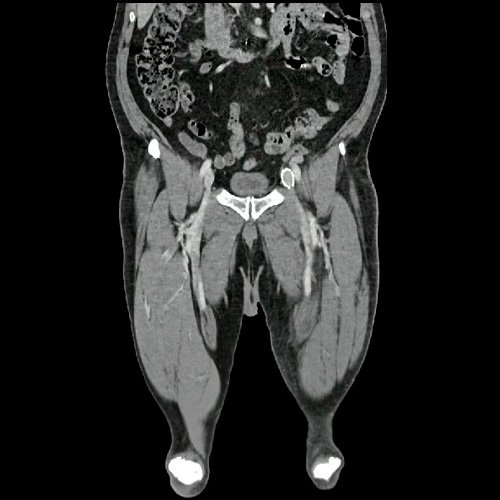

• AngioTAC de miembros inferiores (Día 2): Ateromatosis parietal calcificada parcheada en todo el territorio aorto-ilíaco-femoral bilateral. LADO DERECHO: Arteria ilíaca interna: de calibre y trayecto conservado, permeable. Arterias ilíaca externa y femoral común: de calibre y trayecto conservados, permeables. Arterias circunfleja ilíaca superficial y epigástrica superficial: de calibre y trayecto conservados, permeables. Arteria femoral superficial: de calibre y trayecto conservado, permeable. Arteria femoral profunda: de calibre y trayecto conservado, permeable. Arterias circunflejas femoral medial y lateral: de calibre y trayecto conservados, permeables. Arteria poplítea: de calibre y trayecto conservado, permeable. Arteria tibial anterior: de calibre y trayecto conservado, permeable. Arteria tibial posterior: de calibre y trayecto conservado, permeable. Vena ilíaca primitiva: 13 mm, vena ilíaca externa 11 mm, vena ilíaca interna 7 mm. LADO IZQUIERDO: En esta ocasión, en fase angiográfica se observa de calibre y opacificación conservada de las arterias femoral superficial y profunda, poplítea y de sus ramas musculares en muslo y pierna. En fase venosa se evidencia un defecto de relleno endoluminal de la vena primitiva izquierda que impresiona extenderse actualmente a la vena iliaca externa, a la vena femoral superficial y poplítea, hasta nivel del hueco homonimo, las cuales se visualizan aumentadas de calibre con respecto a sus contralaterales, en relación a trombosis venosa profunda. Se sugiere cotejar con ecodoppler de miembros inferiores. No se identifica compromiso de la porción visualizada de la vena cava inferior ni del sistema venoso ilíaco contralateral. Se visualiza dispositivo vascular en VCI (filtro VCI), infrayacente a las venas renales. Presenta aumento del diámetro del muslo izquierdo con respecto a su contralateral, asociado a edema de los tejidos blandos superficiales. Reticulación de la grasa de la región inguinal a predominio izquierdo con algunas burbujas aéreas. Se observa inmediatamente infrayacente a los antes mencionado, un área hiperdensa que realza en fase venosa, con centro hipodenso, que mide 2.2 cm x 1.4 cm, ya visualizado en tomografía previa. Cambios artrodegenerativos coxo-femorales y tricompartimentales en la rodilla. Signos de entesopatía cuadricipital distal. No se observan alteraciones a nivel del fémur ni de las porciones visualizadas de la tibia y el peroné. Arteria ilíaca interna: de calibre y trayecto conservado, permeable. Arterias ilíaca externa y femoral común: de calibre y trayecto conservados, permeables. Arterias circunfleja ilíaca superficial y epigástrica superficial: de calibre y trayecto conservados, permeables. Arteria femoral superficial: de calibre y trayecto conservado, permeable. Arteria femoral profunda: de calibre y trayecto conservado, permeable. Arterias circunflejas femoral medial y lateral: de calibre y trayecto conservados, permeables. Arteria poplítea, tibial anterior y tibial posterior: de calibre disminuido con respecto a su contralateral, permeables. Vena ilíaca primitiva: 14 mm, vena ilíaca externa 17 mm, vena ilíaca interna 9 mm. Calcificaciones en conducto inguinal bilateral. Hidrocele bilateral.

• Flebotomografia de miembros inferiores (Día 18): Filtro de vena cava inferior infrayacente a venas renales. Stent metálico a nivel de la vena ilíaca común y externa izquierda, permeable. Se explora la región venosa del territorio femoral y poplíteo, evidenciándose defectos parciales de relleno endoluminal a nivel de la vena femoral superficial y profunda izquierdas, compatibles con trombosis venosa parcial. A nivel del tercio distal de la vena femoral común izquierda, se evidencia aumento de calibre e interrupción brusca de la opacificación del contraste (“signo de stop”), compatible con trombosis venosa oclusiva en dicho nivel, sin opacificación venosa distal. Se observan similares hallazgos a nivel de la vena femoral superficial contralateral, evidenciándose defectos de relleno endoluminal parcial hasta su tercio distal, con ausencia de opacificación distal. Salvo mejor criterio sugiero complementar con eco-Doppler de venoso de ambos miembros inferiores. Presenta edema difuso de los tejidos blandos de miembro inferior izquierdo. Se observa en los tejidos blandos de la región inguinal izquierda, colección hipodensa con realce periférico que mide 4.7 cm AP x 4 cm. Además se observan ganglios locorregionales aumentados en número y tamaño, algunos de rango megálico.

Angio TAC de miembros inferiores (Día 2)

Flebotomografia de miembros inferiores (Día 18)